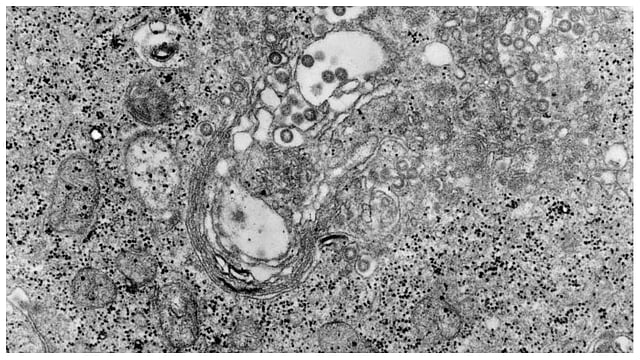

أعلنت وزارة الثروة الحيوانية بموريتانيا، مساء أمس الخميس، ارتفاع حالات الاصابة بحمى الوادي المتصدع إلى خمس وتسعين حالة، مؤكدة أنها تتوزع على خمس بؤر.

وأوضحت الوزارة، أنها تأكدت من خمس وتسعين إصابة بهذا الوباء تم تشخيصها إثر تحاليل على 465 عينة مشتبه فيها في خمس محافظات.